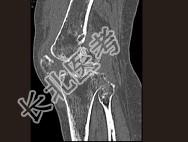

- 单项选择题男,36岁, 膝关节疼痛8年余,活动受限, 其周围可触及肿块,结合图像, 最可能的诊断是 ( )

A、骨巨细胞瘤

B、滑膜肉瘤

C、血友病性关节炎

D、色素沉着绒毛结节性滑膜炎

E、类风湿关节炎